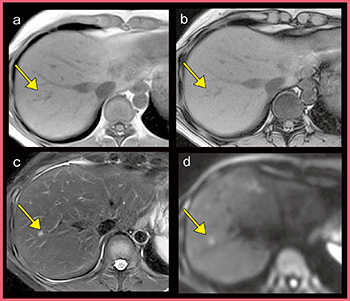

●転移性肝腫瘍における有用性

図1は,30歳代の女性で,転移性肝腫瘍の疑いによりMRI検査が実施された。いずれのシーケンスにおいても良好な画像が得られており,肝腫瘍診断で重要なT2強調画像(図1 c)や拡散強調画像(DWI)(d)も含めて,微小な病変の信号がはっきりと描出されている。

図1 転移性肝腫瘍症例のルーチン検査画像

a:in phase b:out-of-phase

c:T2強調画像 d:DWI(b=1000s/mm2)